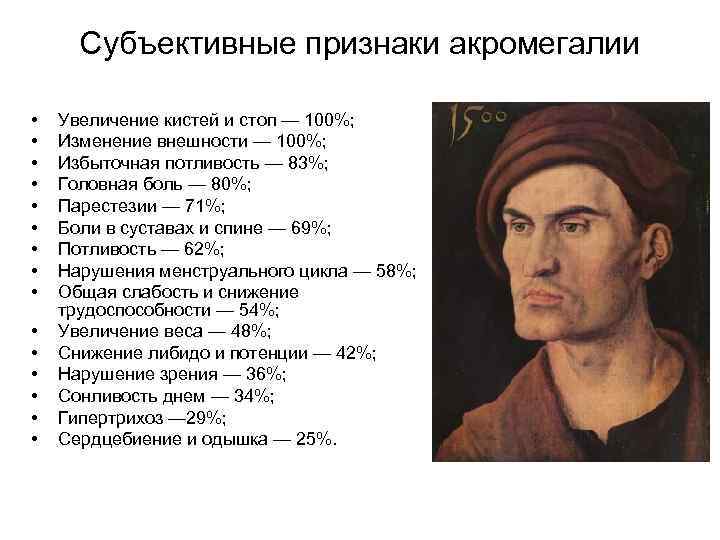

Субъективные признаки акромегалии • • • • Увеличение кистей и стоп — 100%; Изменение внешности — 100%; Избыточная потливость — 83%; Головная боль — 80%; Парестезии — 71%; Боли в суставах и спине — 69%; Потливость — 62%; Нарушения менструального цикла — 58%; Общая слабость и снижение трудоспособности — 54%; Увеличение веса — 48%; Снижение либидо и потенции — 42%; Нарушение зрения — 36%; Сонливость днем — 34%; Гипертрихоз — 29%; Сердцебиение и одышка — 25%.

Субъективные признаки акромегалии • • • • Увеличение кистей и стоп — 100%; Изменение внешности — 100%; Избыточная потливость — 83%; Головная боль — 80%; Парестезии — 71%; Боли в суставах и спине — 69%; Потливость — 62%; Нарушения менструального цикла — 58%; Общая слабость и снижение трудоспособности — 54%; Увеличение веса — 48%; Снижение либидо и потенции — 42%; Нарушение зрения — 36%; Сонливость днем — 34%; Гипертрихоз — 29%; Сердцебиение и одышка — 25%.